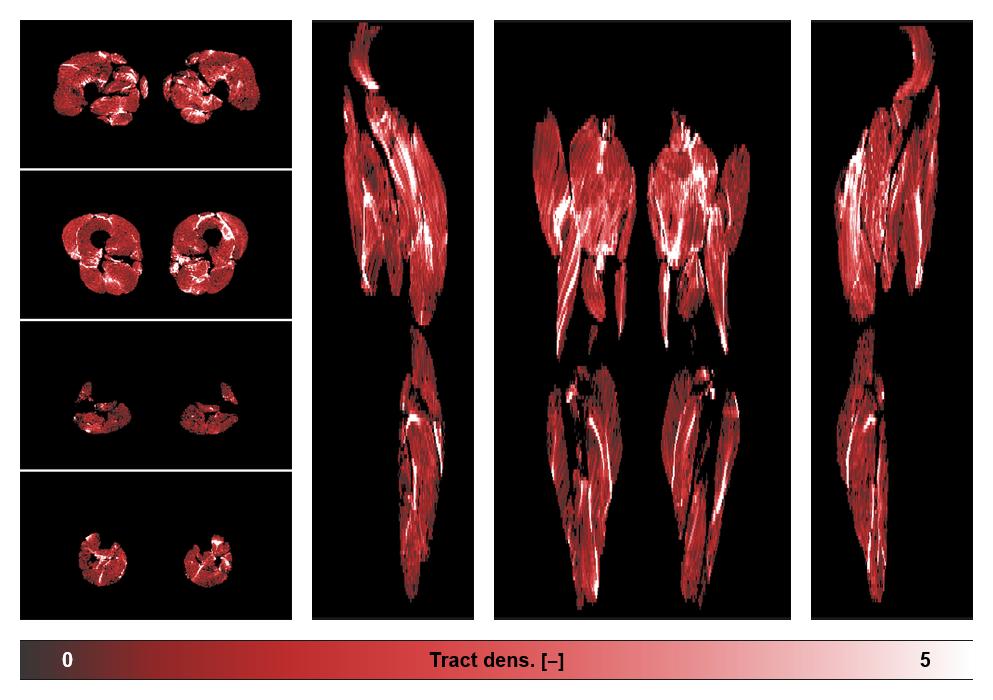

• Muscle fiber density map

Muscle fiber tract density map based on whole leg DTI based fiber tractography.